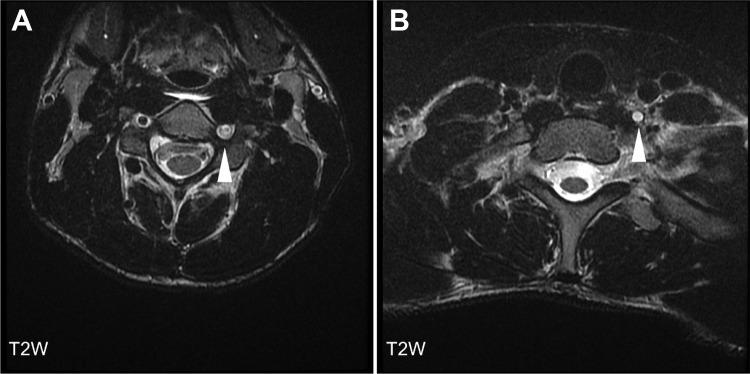

Lateral medullary syndrome is rare in pediatrics. It is characterized by neurological deficits due to an ischemic lesion in the lateral medulla. The authors describe a 17-year-old boy who developed lateral medullary syndrome in the context of a hyperflexion neck injury while diving in shallow water with traumatic vascular injury. He had "crossed" neurological deficits above and below the neck. His magnetic resonance angiography showed intra- and extracranial left vertebral artery occlusion and his magnetic resonance imaging showed signal abnormality involving the left lateral medulla and inferomedial cerebellum in keeping with an infarct secondary to left vertebral artery and left posterior inferior cerebellar artery occlusion. Good neurological recovery was observed on heparin therapy started after surgical treatment of traumatic injury. To our knowledge, this is the first reported case of lateral medullary syndrome in a pediatric population related to a flexion neck injury. The authors emphasize the importance of a high level of suspicion for accurate diagnosis.

外侧延髓综合征在儿科中较为罕见。它的特征是由于外侧延髓的缺血性病变导致神经功能缺损。作者描述了一名17岁男孩,他在浅水中潜水时因颈部过度屈曲损伤伴外伤性血管损伤而患上外侧延髓综合征。他在颈部上下出现了“交叉性”神经功能缺损。他的磁共振血管造影显示颅内和颅外左侧椎动脉闭塞,磁共振成像显示左侧外侧延髓和小脑下内侧信号异常,符合左侧椎动脉和左侧小脑后下动脉闭塞继发的梗死。在对外伤进行手术治疗后开始肝素治疗,观察到神经功能恢复良好。据我们所知,这是首次报道的儿科人群中与颈部屈曲损伤相关的外侧延髓综合征病例。作者强调了高度怀疑对于准确诊断的重要性。